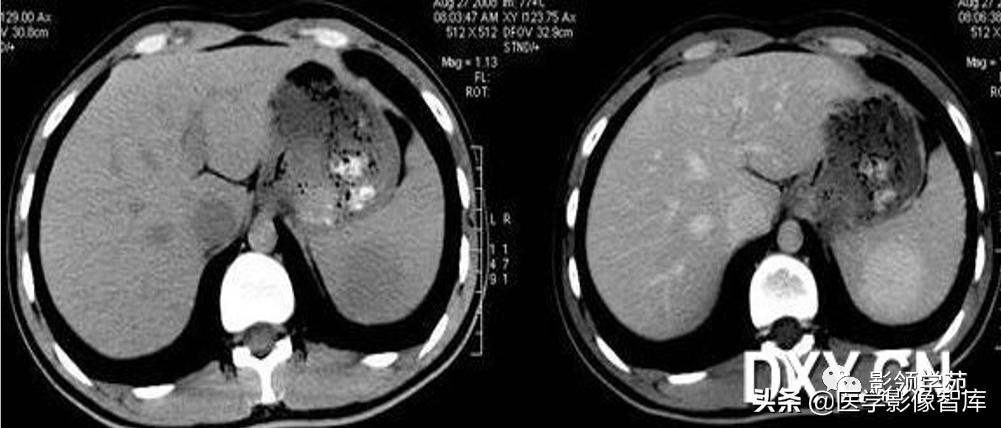

【CT表现】

CT平扫:

1)脾脓肿早期表现为脾弥漫性肿大,密度稍低且均匀。

2)发生液化坏死后,见圆形或椭圆形低密度区,CT值大多在20HU左右,边界不清。

3)少数脓肿内可见小气泡或气液平面为特征性表现。

增强扫描:见脓肿壁明显强化,中心坏死区无强化。当脓肿为多发而又较小时,则常表现为增强后脾内斑点状或粟粒状低密度灶。